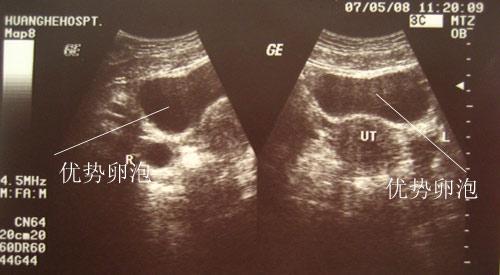

第三个,用B超检查

这个方法是最科学的,也是最靠谱的一个方法。在月经周期8--10天左右,我们就可以去医院通过B超去观察卵泡的生长,前期2天检查一次,当卵泡慢慢长大,直径到了16mm的时候就改为每天检查一次,卵子的直径达到18~25cm时就代表已经成熟了,一般会在一到两天内排卵,可以根据医生的建议安排好时间做运动了。